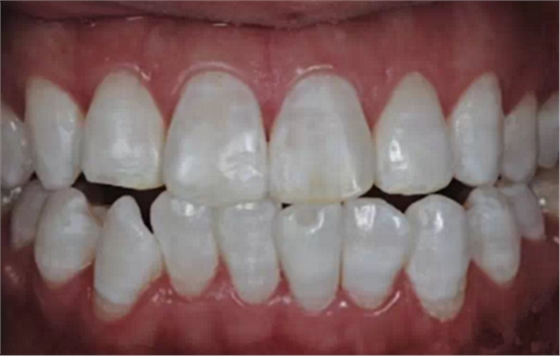

飲用水是攝入氟的一個(gè)最大來源,但為了達(dá)到治療/修復(fù)氟牙癥的目的,除了改良水源,適量攝氟以外,有輕度著色而無(wú)缺損的氟牙癥患者可以采用漂白脫色法脫色進(jìn)行牙齒治療/修復(fù);中度及重度染色或有缺損的患者可用美國(guó)皓齒的居家美白套裝PF,Opalustre微研磨劑和Edelweiss激光樹脂貼面等方法修復(fù)。

目前臨治療/修復(fù)中,比較常用到的還是Opalustre微研磨劑。